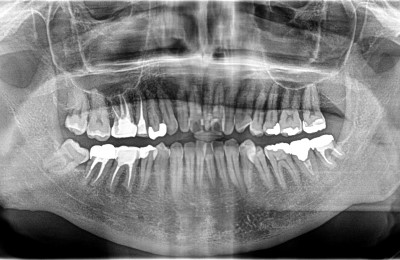

CASE02精密根管治療

Before

After

| 主訴 | 左右の奥歯の歯茎が腫れた。 |

|---|---|

| 治療方法 | 右下6番目、左下8番目の歯に大きな根尖病変(膿の袋)が認められる。また、右上6番目にも根尖病変、右上5番目に不良な根管充填が認められる。 ラバーダム防湿および拡大視野下にてそれぞれ精密根管治療を行った。 |

| 治療期間 | 約6ヶ月 (1歯あたり2~3回。治療後の経過観察期間も含める。) |

| リスク | 治療後、病変が再発したり治癒しなかった場合は外科処置が必要となる場合がある。 歯根破折が認められた場合は抜歯適応となる。 |

| 費用 | 110,000円(小臼歯)×1 132,000円(大臼歯)×3 ※被せ物の料金は別途88,000円×本数かかります。 |